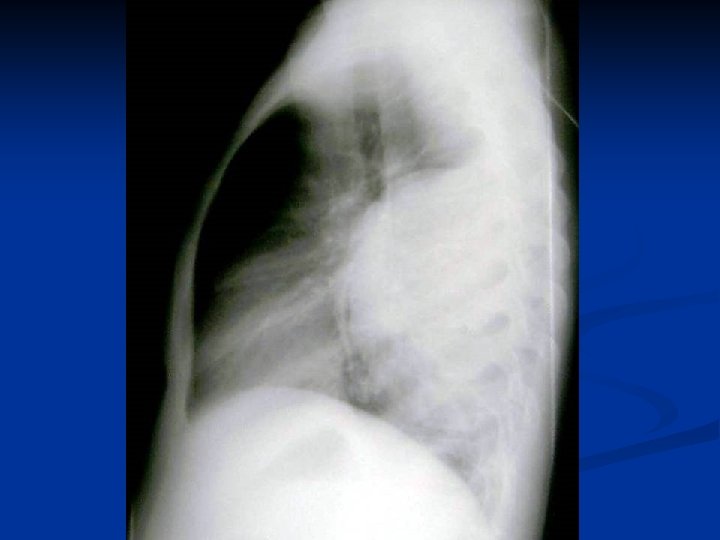

Caracteristici generale n n n Boala parazitara determinata de Taenia echinococcus granulosus. Descrisa inca de pe vremea lui Hipocrat si a lui Galen. Termenul de “chist hidatic” utilizat de Rudolphi in 1908. Localizarea pulmonara este a doua ca frecventa dupa cea hepatica. Boala cu distributie endemica in regiunea mediteraneana, Orientul Mijlociu, Australia, Noua Zeelanda, America de Sud.

Metode de diagnosticare